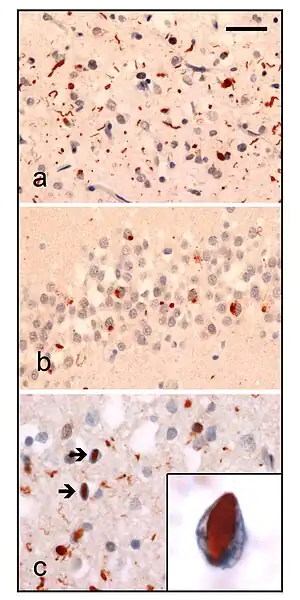

| Neuropathologic analysis of brain tissue from FTLD-TDP patients. Ubiquitin immunohistochemistry in cases of familial FTLD-TDP demonstrates staining of (a) neurites and neuronal cytoplasmic inclusions in the superficial cerebral neocortex, (b) neuronal cytoplasmic inclusions in hippocampal dentate granule cells, and (c) neuronal intranuclear inclusions in the cerebral neocortex (arrows). Scale bar; (a) and (b) 40 μm, (c) 25 μm, insert 6 μm. | |

- FTLD-TDP (or FTLD-U ) is characterised by ubiquitin and TDP-43 positive, tau negative, FUS negative inclusion bodies. The pathological histology of this subtype is so diverse it is subdivided into four subtypes based on the detailed histological findings:

- Type A presents with many small neurites and neuronal cytoplasmic inclusion bodies in the upper (superficial) cortical layers. Bar-like neuronal intranuclear inclusions can also be seen they are fewer in number.

- Type B presents with many neuronal and glial cytoplasmic inclusions in both the upper (superficial) and lower (deep) cortical layers, and lower motor neurons. However neuronal intranuclear inclusions are rare or absent. This is often associated with ALS and C9ORF72 mutations (see next section).

- Type C presents many long neuritic profiles found in the superficial cortical laminae, very few or no neuronal cytoplasmic inclusions, neuronal intranuclear inclusions or glial cytoplasmic inclusions. This is often associated with semantic dementia.

- Type D presents with many neuronal intranuclear inclusions and dystrophic neurites, and an unusual absence of inclusions in the granule cell layer of the hippocampus. Type D is associated with VCP mutations.